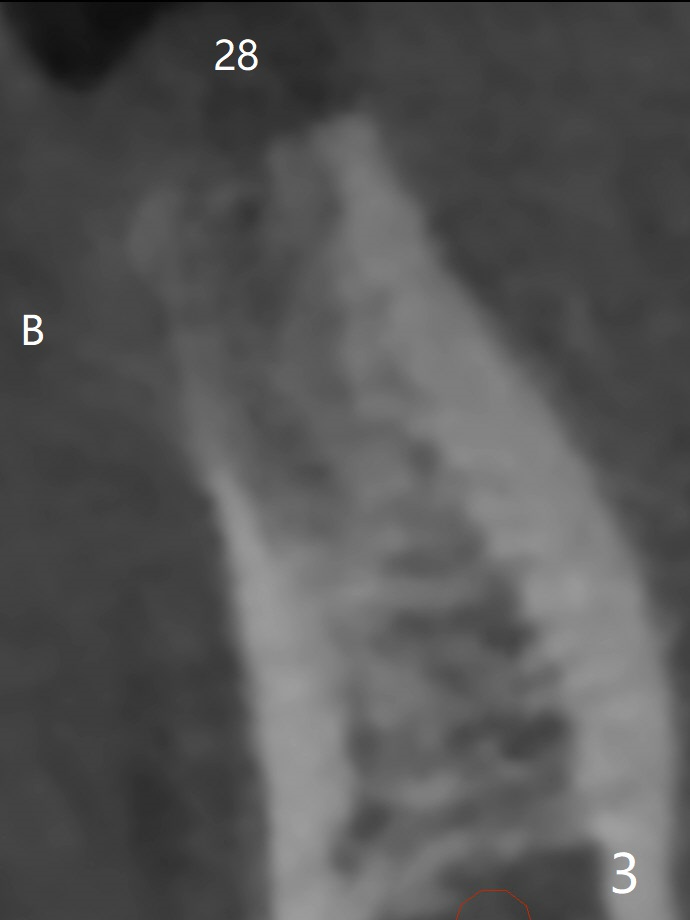

Bone Density Post Extraction with or without Bone Graft

Edentulous Lower Molar